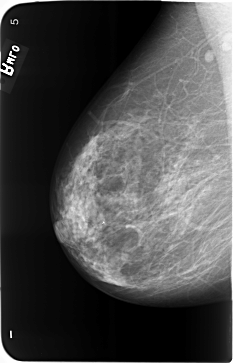

B_3493_1.RIGHT_MLO

RIGHT_CC LINES 5808 PIXELS_PER_LINE 3664 BITS_PER_PIXEL 12 RESOLUTION 50 NON_OVERLAY

RIGHT_MLO LINES 5808 PIXELS_PER_LINE 3728 BITS_PER_PIXEL 12 RESOLUTION 50 NON_OVERLAY